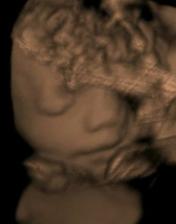

..Matulka se narodil 1.7.08 (36+4), vážil 3,18kg, měřil 50 cm, což nebylo málo 🙂 Pár hodin po porodu se ale vyskytly komplikace, pomalu se mu vstřebávala plodová voda, proto byl umístěn do inkubátoru a napojen na kyslík. Měl potíže i se zažíváním, takže mu byla podávána výživa kapačkami. PO dvou dnech mu začaly sestřičky dávat moje mlíčko stříkačkou a Matulka se začal lepšit. Nicméně zhubnul přes 40 dkg, a byl hodně vyčerpaný. V inkubátoru strávil týden. Po té ho dali do postýlky, ale pořád přespával u sestřiček na novorozenecké JIPce. CHodila jsem za ním každé tři hodky, kdo zažil, ví, kdo nezažil toho děsit nebudu, ale vzpomínky na tuto dobu nemám nejpříjemnější. Další týden jsem si ho pak mohla ´půjčovat´ - vlastní děťátko.. Bylo to nejkrutějších 14 dní v mém životě. Nicméně ted je Matulkovi skoro 8 týdnů a všechno dohnal, v lecčem je dokonce napřed. Je to velmi živé, veselé a věčně hladové miminko 🙂 uf uf .)